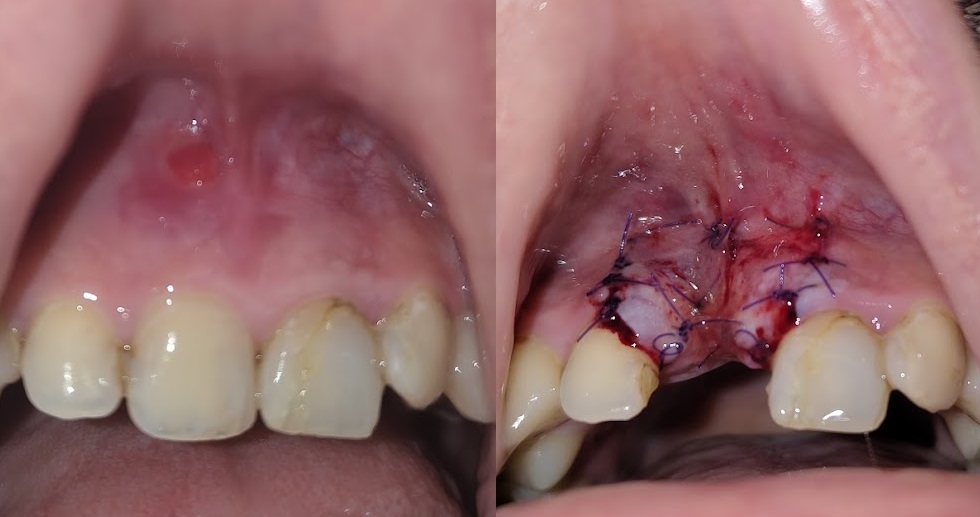

Сделали мне цистэктомию с удалением зуба переднего (резца), консервативное лечение не помогло, попутно разъебали всю кость-десну и теперь огромный провал-долина на месте где зуб был. По КТ уже было видно огромную площадь кисты и сразу сказали что костную пластику надо делать, хотели сразу после удаления но хирург разрезав сказала что киста рыхлая и хуевая и не будет делать пластику т.к. высок риск отторжения материала.

Пока что зашила меня и отправила отдыхать, через неделю осмотр, примерно через месяц сказала можно подумать будет над пластикой.

Алсо подскажите мне, нужно ли мне с имплантологом сразу до костной пластики знакомится-работать показаться или пластикой задача челюстно-лицевого хирурга заниматься, а к импантологу уже после месяца через 6 после пластики?